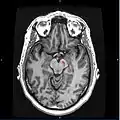

Substantia nigra highlighted in red.

Section through superior colliculus showing substantia nigra.